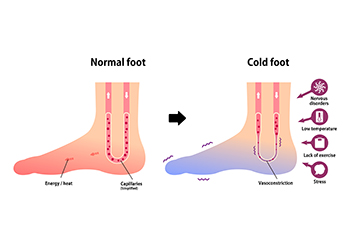

Cold Feet After Exercising

Cold Feet After ExercisingIf your feet feel cold during or right after exercising, when the rest of your body feels warm, it may be a sign that something is wrong. It can be as simple as wearing shoes or socks that are too tight and restrict proper blood flow to the...